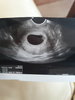

15296838121351895087511.jpg u mnie wyglądało tak w 5tyg3d

Załączniki

• 15296838121351895087511.jpg

15296838121351895087511.jpg

1,4 MB · Wyświetleń: 108